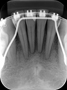

Radiografia Periapical